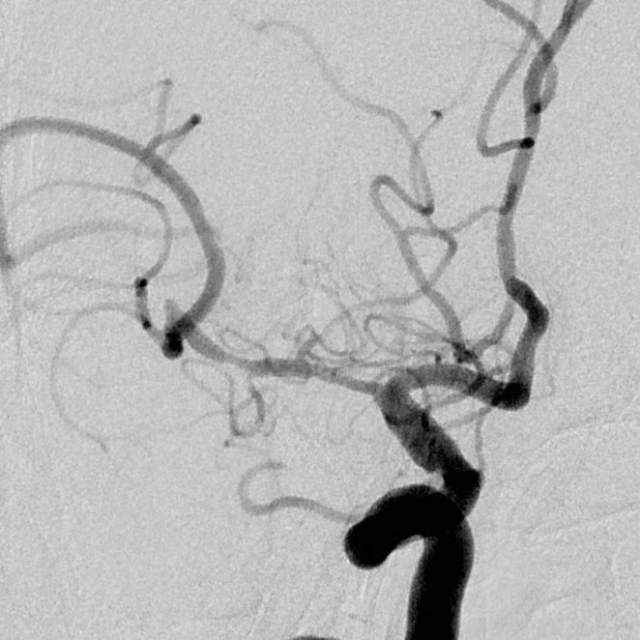

3、第三个患者:我们给予一期外科干预后,一个月后TTP检查发现,狭窄的部位和术后即刻相比是变差的,但与第一次术前相比好转。继续药物治疗狭窄部位存在进行性闭塞的风险。于是二期安全的植入支架,血流完全恢复正常,顺利出院。

一期干预后,一个月复查所见狭窄区为长节段、多发部位狭窄,与术后即刻相比变差了

继续药物治疗存在狭窄部位闭塞的风险,果断给予支架植入

支架植入后,重建后血管的形态,血流完全恢复,顺利出院